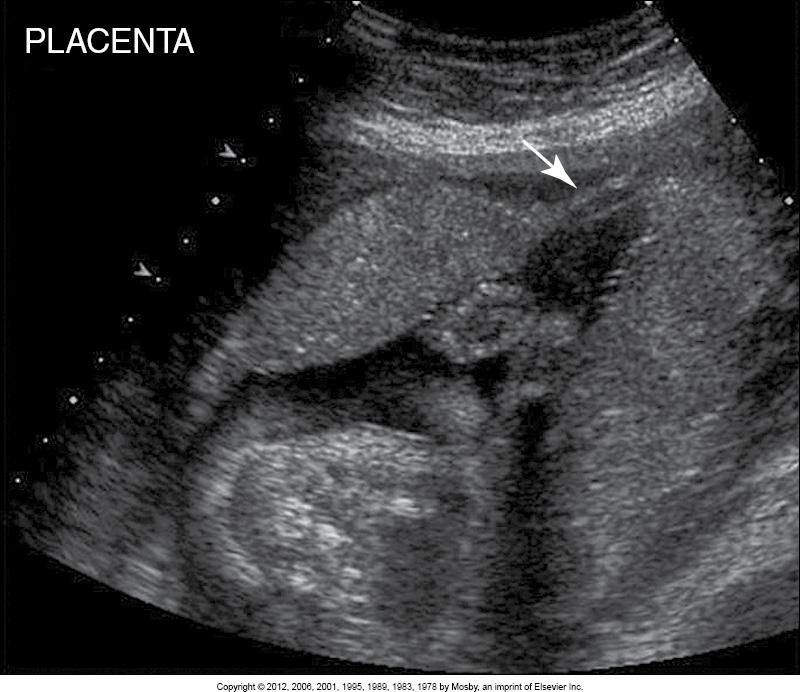

What are the arrows pointing to?

circumvallate/circummarginate placenta